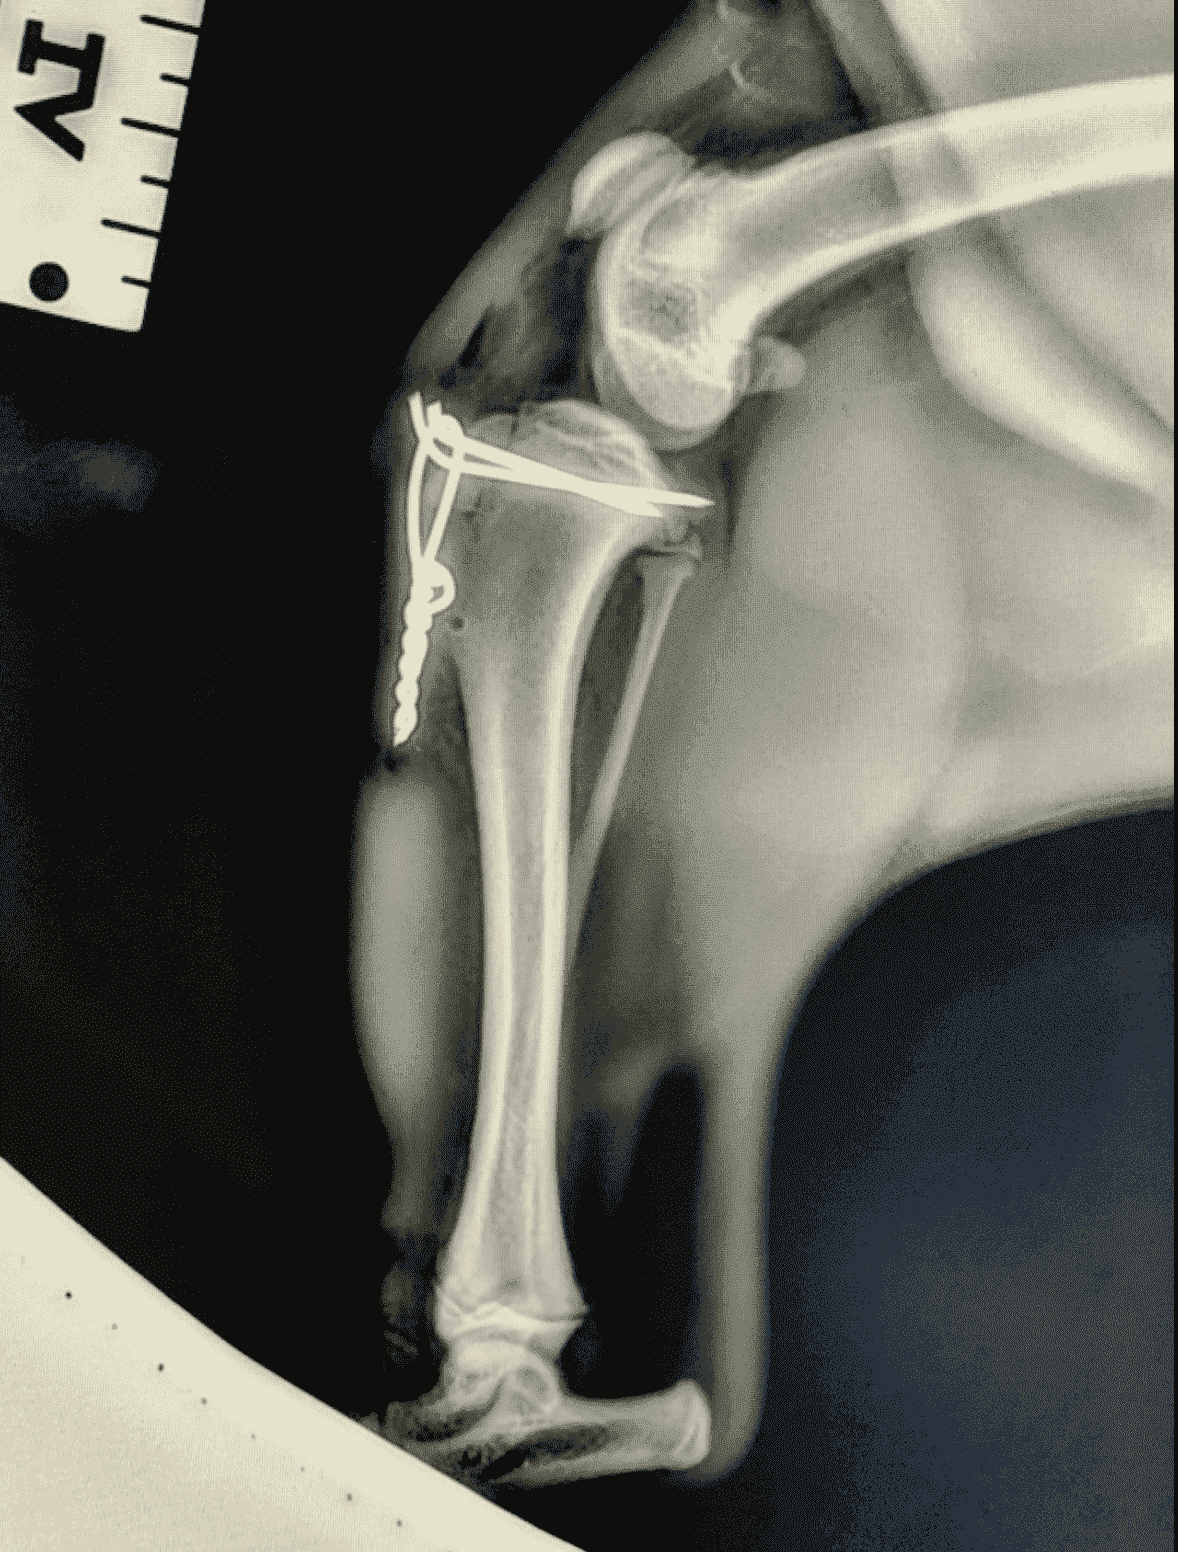

After discussion with the owners, we elected to proceed with surgery to repair the tibial crest avulsion (fracture). Given that we could do this surgery in the clinic, it did not require a referral to a specialist (like the pacemaker case above). The veterinary nurses assisted in preparing the patient for anaesthesia and preparing the surgical site – read our previous blog about anaesthesia in veterinary medicine.

The fracture was repaired with tension bands; see the x-ray attached. The implants will not be removed and will remain in the stifle. After rest and progressive controlled exercise, the fracture site will heal, and little Fred will return to running and playing in no time!